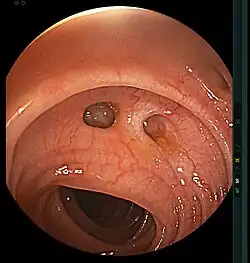

- Les diverticules du côlon, bien que découverts fortuitement lors d'une coloscopie, peuvent s'infecter (voir diverticulite) et se perforer, ce qui nécessite une intervention chirurgicale[6].